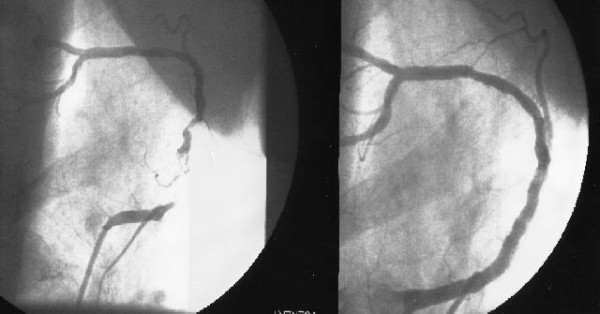

X-rays of my Right Coronary Artery, before and after placement of two stents on a 4cm length (OSHKOSH, 29th JULY 2005)